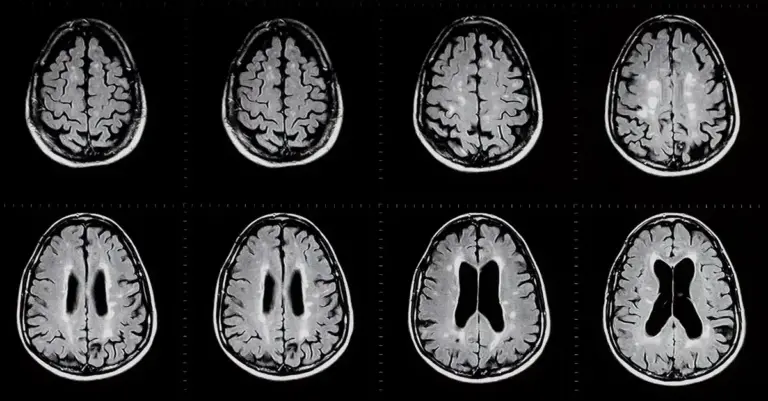

Beyin Görüntüleme: MRI ve CT taramaları, beyindeki anormallikleri görmek için kullanılabilir. Beyindeki tümörler, kanamalar veya anormal yapılar bu testlerle tespit edilebilir.